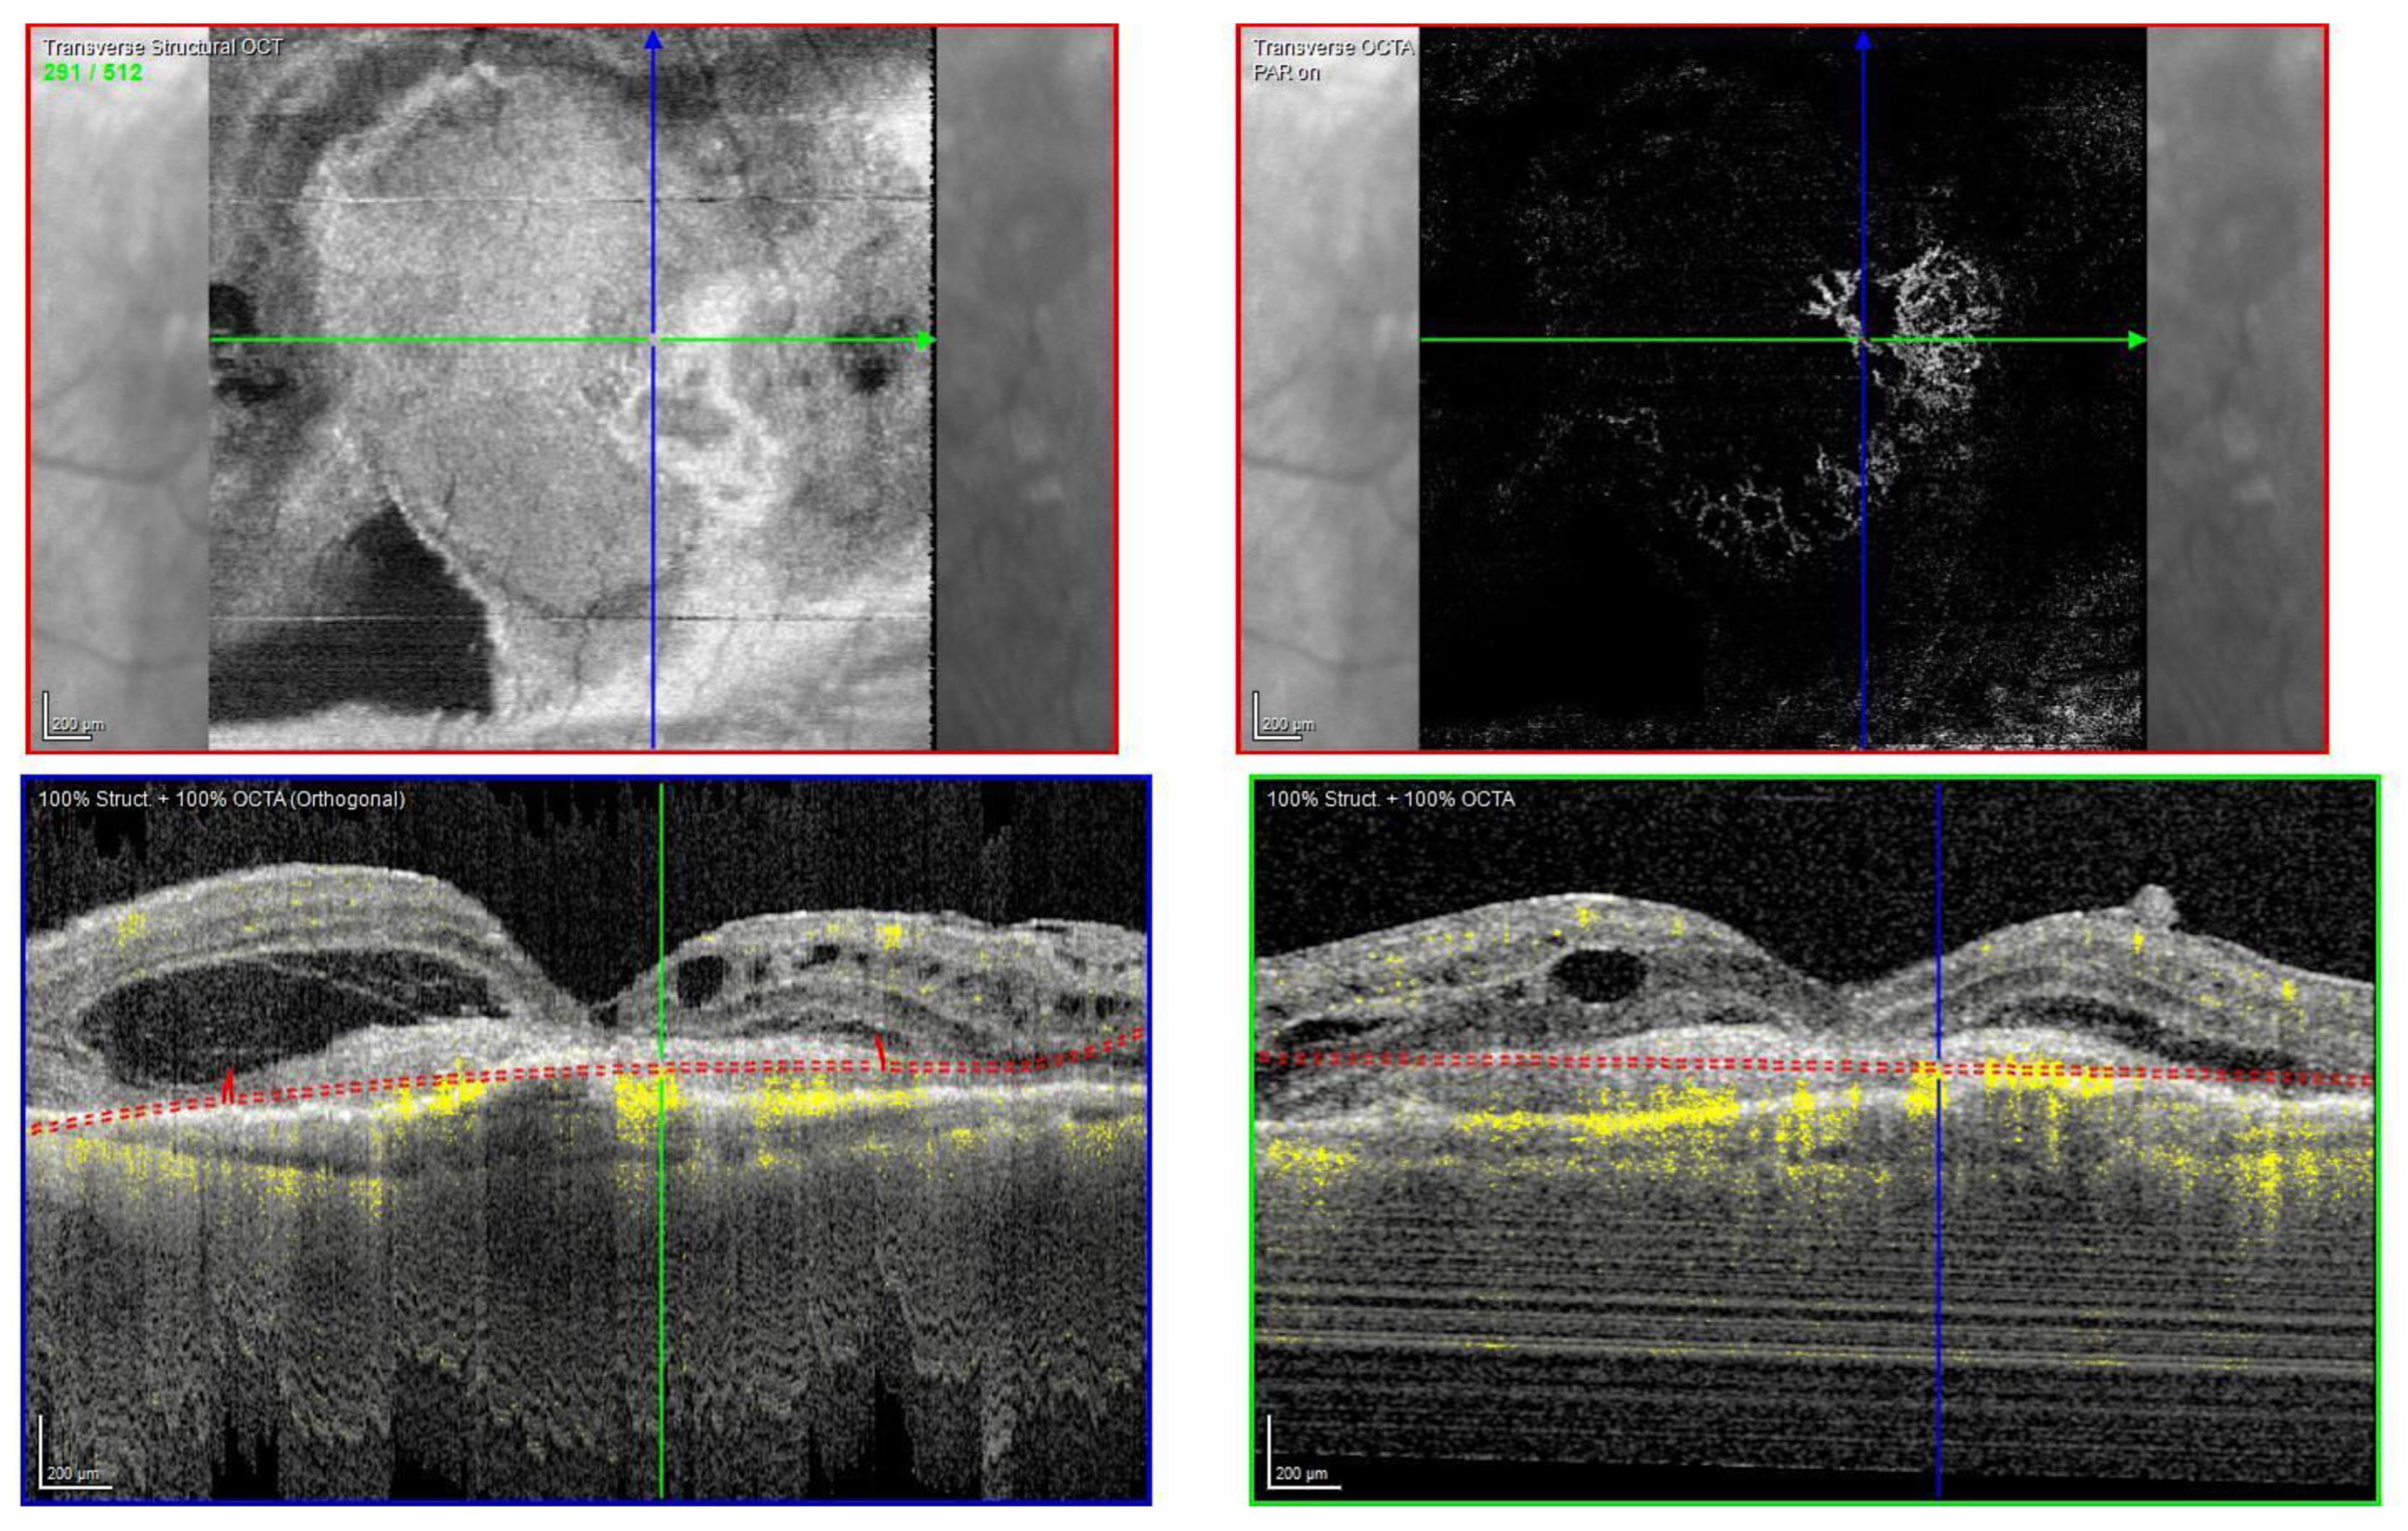

The OCT scan showed a dry macula with drusen in the right eye and a type 1 MNV with PEDs, intraretinal and subretinal fluid, subretinal haemorrhage, and a haemorrhagic BALAD in the left eye (Figure 9A).

Figure 9.

Case 6. (A) Heidelberg Spectralis optical coherence tomography shows a type 1 MNV with fibrovascular pigment epithelial detachment, subretinal and intraretinal fluid, and haemorrhagic BALAD in the left eye. (B,C) Heidelberg Spectralis optical coherence tomography shows a good response after a year and two years of intravitreal anti-VEGF treatment, respectively.

The OCTA scan confirmed the presence of the left MNV.

A T&E regimen with anti-VEGF intravitreal injection therapy was commenced. The patient showed an initial good response to the treatment (Figure 9B). Unfortunately, over the following years, the worsening of the condition was observed despite treatment. Thus, the patient switched to a different anti-VEGF molecule.

To date, the patient is still on treatment. The left BCVA was 0.4 logMAR when last examined. The last OCT scan showed intraretinal fluid and an improved BALAD (Figure 9C).